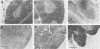

Thymocytes from mice 2 weeks after infection with Toxoplasma gondii resisted natural killer (NK) cell-mediated cytolysis in contrast to the high sensitivity of normal mouse thymocytes. The infected mouse thymocytes also failed to form conjugates with effector cells and to compete for cytolysis of NK sensitive targets. These effects were mediated, at least in part, by interferon-gamma because normal thymocytes became NK insensitive after incubation in the infected mouse serum which contained significant amount of interferon-gamma, and pH 2 treatment of the serum abolished the effect. An alternate possibility for the reduced NK sensitivity of the infected mouse thymocytes was the elimination of NK-sensitive cells from the thymus, since histopathological studies showed marked atrophy and clearance of NK-sensitive thymocytes in the cortex of thymuses of infected mice. Although T. gondii induced augmentation followed by suppression of the host splenic NK activity, it seems unlikely that this altered NK activity was responsible for the lowered NK sensitivity of the thymocytes.